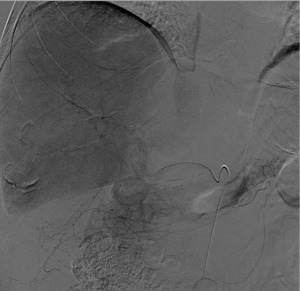

Angiographic lesion vascular grade assessment

Visual vascular grading of the lesions was performed using images obtained during diagnostic angiography. For each patient, two board-certified interventional radiologists blinded to the treatment regimen reviewed the digital subtraction angiograms. Angiographic tumor vascularity was categorized into 4 grades for each patient. We conducted our visual rating inspired by rating systems used in a study focusing on recurrent glioblastoma multiforme and anaplastic astrocytomas (10), another study utilizing digital subtraction angiography (DSA) for visual rating in gliomas (11), and research on the vascularization of liver metastases (12). The angiographic tumor vascularity of each patient was classified as follows: grade 1, avascular tumors; grade 2, mild tumor flushing; grade 3, tumor flushing with an arterial network; and grade 4, abnormal vascularization and arteriovenous shunting (Figures 1-4). Compared with the reference study (12), the lesions of patients with grade 1 and 2 tumors in our study showed similar or less contrast enhancement than the normal parenchyma, aligning with the hypovascular class in the reference. In contrast, the lesions of patients with grade 3 and 4 tumors, which exhibited a higher contrast than the surrounding hepatic parenchyma, corresponded to the hypervascular class in the reference study.